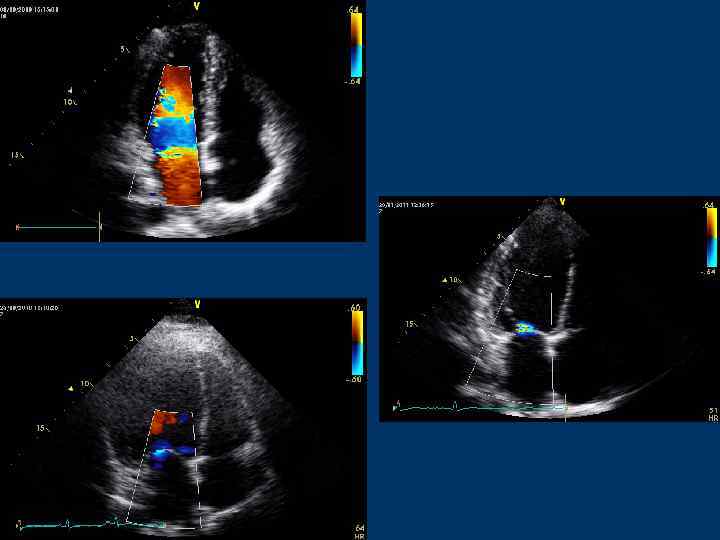

Цветное допплеровское сканирование (Color Doppler)

Color Doppler